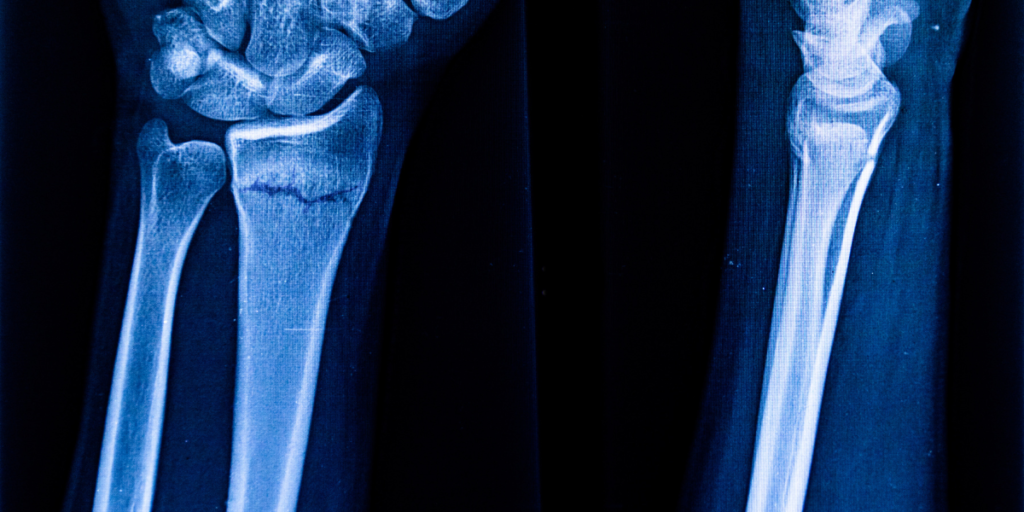

L’Esame RX Avambraccio è una procedura radiografica che utilizza i raggi X per ottenere immagini dettagliate dell’ulna e del radio, le due principali ossa dell’avambraccio. Questo tipo di esame è particolarmente indicato per identificare fratture, lussazioni e altre alterazioni delle strutture ossee e dei tessuti molli circostanti. Grazie alla sua capacità di fornire immagini ad alta risoluzione, l’RX Avambraccio è uno strumento essenziale per il monitoraggio e la diagnosi di molte patologie.

Grazie all’Esame RX Avambraccio, i medici possono ottenere immagini chiare e dettagliate dell’intera struttura ossea dell’avambraccio, inclusi radio e ulna. È possibile visualizzare:

• Fratture recenti e pregresse.

• Microfratture non visibili con altri strumenti diagnostici.

• Lussazioni articolari o instabilità dell’avambraccio.

• Anomalie strutturali come lesioni ossee o calcificazioni.